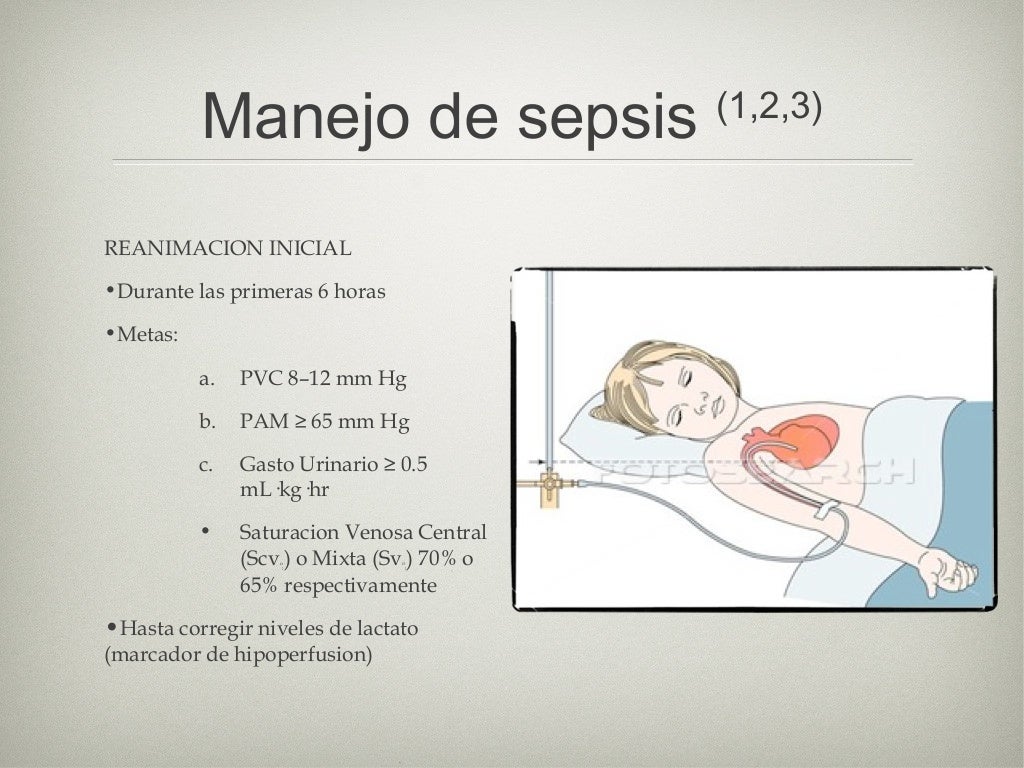

sepsis abdominal Symptoms specific to the type of infection, such as painful urination from a urinary tract infection or worsening cough from pneumonia. Why does abdominal sepsis occur? Abdominal sepsis represents the host’s systemic. Overview an infection can start with a simple injury—like a shallow cut on the arm—that allows bacteria and other microbes to slip into your body’s tissue or circulation. Severe sepsis and septic shock; Without urgent treatment, it can lead to. What causes abdominal pain in sepsis? Although sepsis is a systemic process, the pathophysiological cascade of events may vary from region to region.

Although sepsis is a systemic process, the pathophysiological cascade of events may vary from region to region.